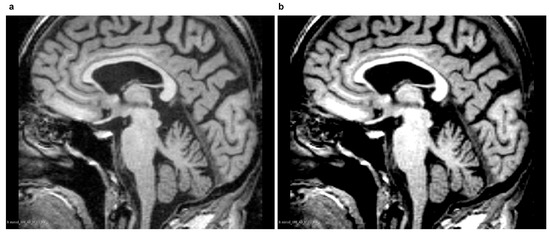

Magnetic Resonance Imaging (MRI) ensures high contrast between various soft tissues, so it is the preferred method of examining the brain, including the CC. In T1-weighted MR images of the brain, acquired in the sagittal plane, the CC has a curved, elongated shape of the inverted letter C, with a high intensity of pixels. An example CC image in the sagittal plane is shown in Figure 1.

Figure 1. The Corpus Callosum (CC) in an example midsagittal brain Magnetic Resonance (MR) image. Data source: Minimal Interval Resonance Imaging in Alzheimer’s Disease (MIRIAD) [11], from the ’miriad_188_1_MR_1’ set.